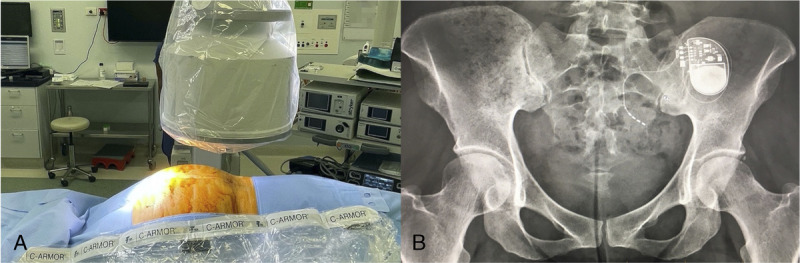

Abstract Image